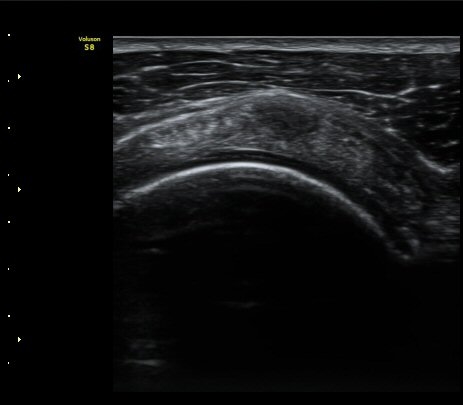

°ß°©ÇÏ±Ù°Ç Á¾´Ü¸é°Ë»ç¿¡¼­ ƯÀÌ ¼Ò°ßÀ» º¸ÀÌÁö ¾ÊÀ½(»çÁø 2, 3)